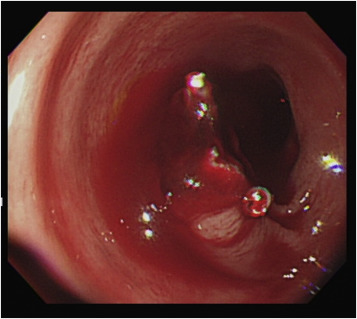

Endoscopic finding of active bleeding from a polypectomy wound. Two endoclips ...

Figure 2.

Endoscopic finding of active bleeding from a polypectomy wound. Two endoclips remained in place.

The two endoclips remained in situ , and active bleeding was observed in the narrow gap between the two endoclips. This finding explained the ineffective clipping and the difficult endoscopic approach to the bleeder source. An attempt with a heat probe, coagulation forceps, and further clipping all failed to approach the bleeder. We further attempted to administer an injection of diluted epinephrine in the base of the stalk remnant, and the remnant slowly began rising, giving the appearance of a new polyp. An endoloop was successfully placed beneath the two previously placed endoclips using the tulip-bundle technique, and the bleeding was successfully controlled ( Figure 3 ). The patient was discharged 3 days later without further bleeding.